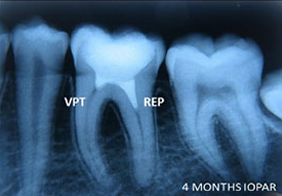

A case of combined REP in one Root and VPT in another Root.

Wound in bone (marked) in one root has healed through REP which is revealed in 6 and 12 months follow up IOPAR, the unaffected pulp in another Root Canal is protected through VPT resulting in the maintenance of validity of Tooth.